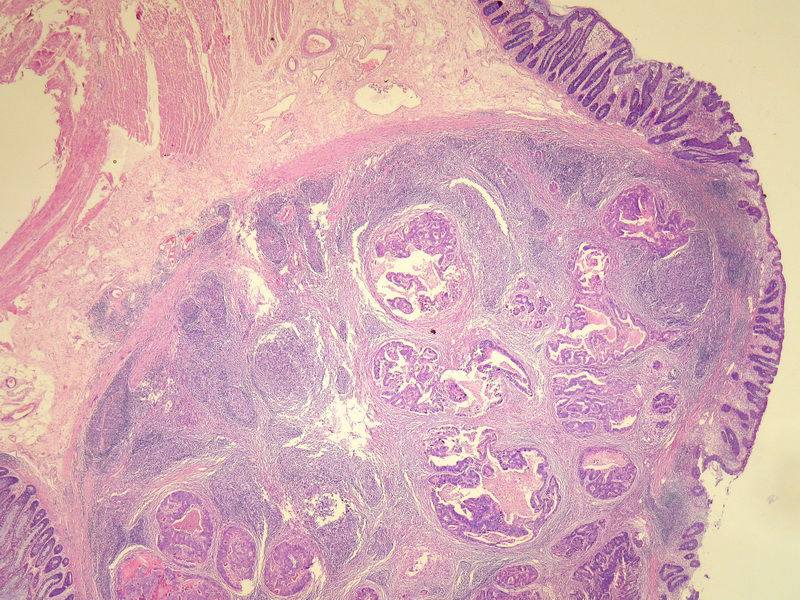

70岁男性,乙状结肠息肉样肿物。

请教:这个乙状结肠肿瘤侵犯到哪一层??图1

×参考诊断

粘膜下层

仅就浸润的深度而言,粘膜下层应该没什么争议。但是肿瘤表面的粘膜腺体是很好的,从低倍图看,不能排除是个转移灶的可能。请临床再查一查除了这个以外别的部位还有没有肿块。

浸润深度为粘膜下层,可粘膜表面的腺体完整,同意楼上的观点。谢谢